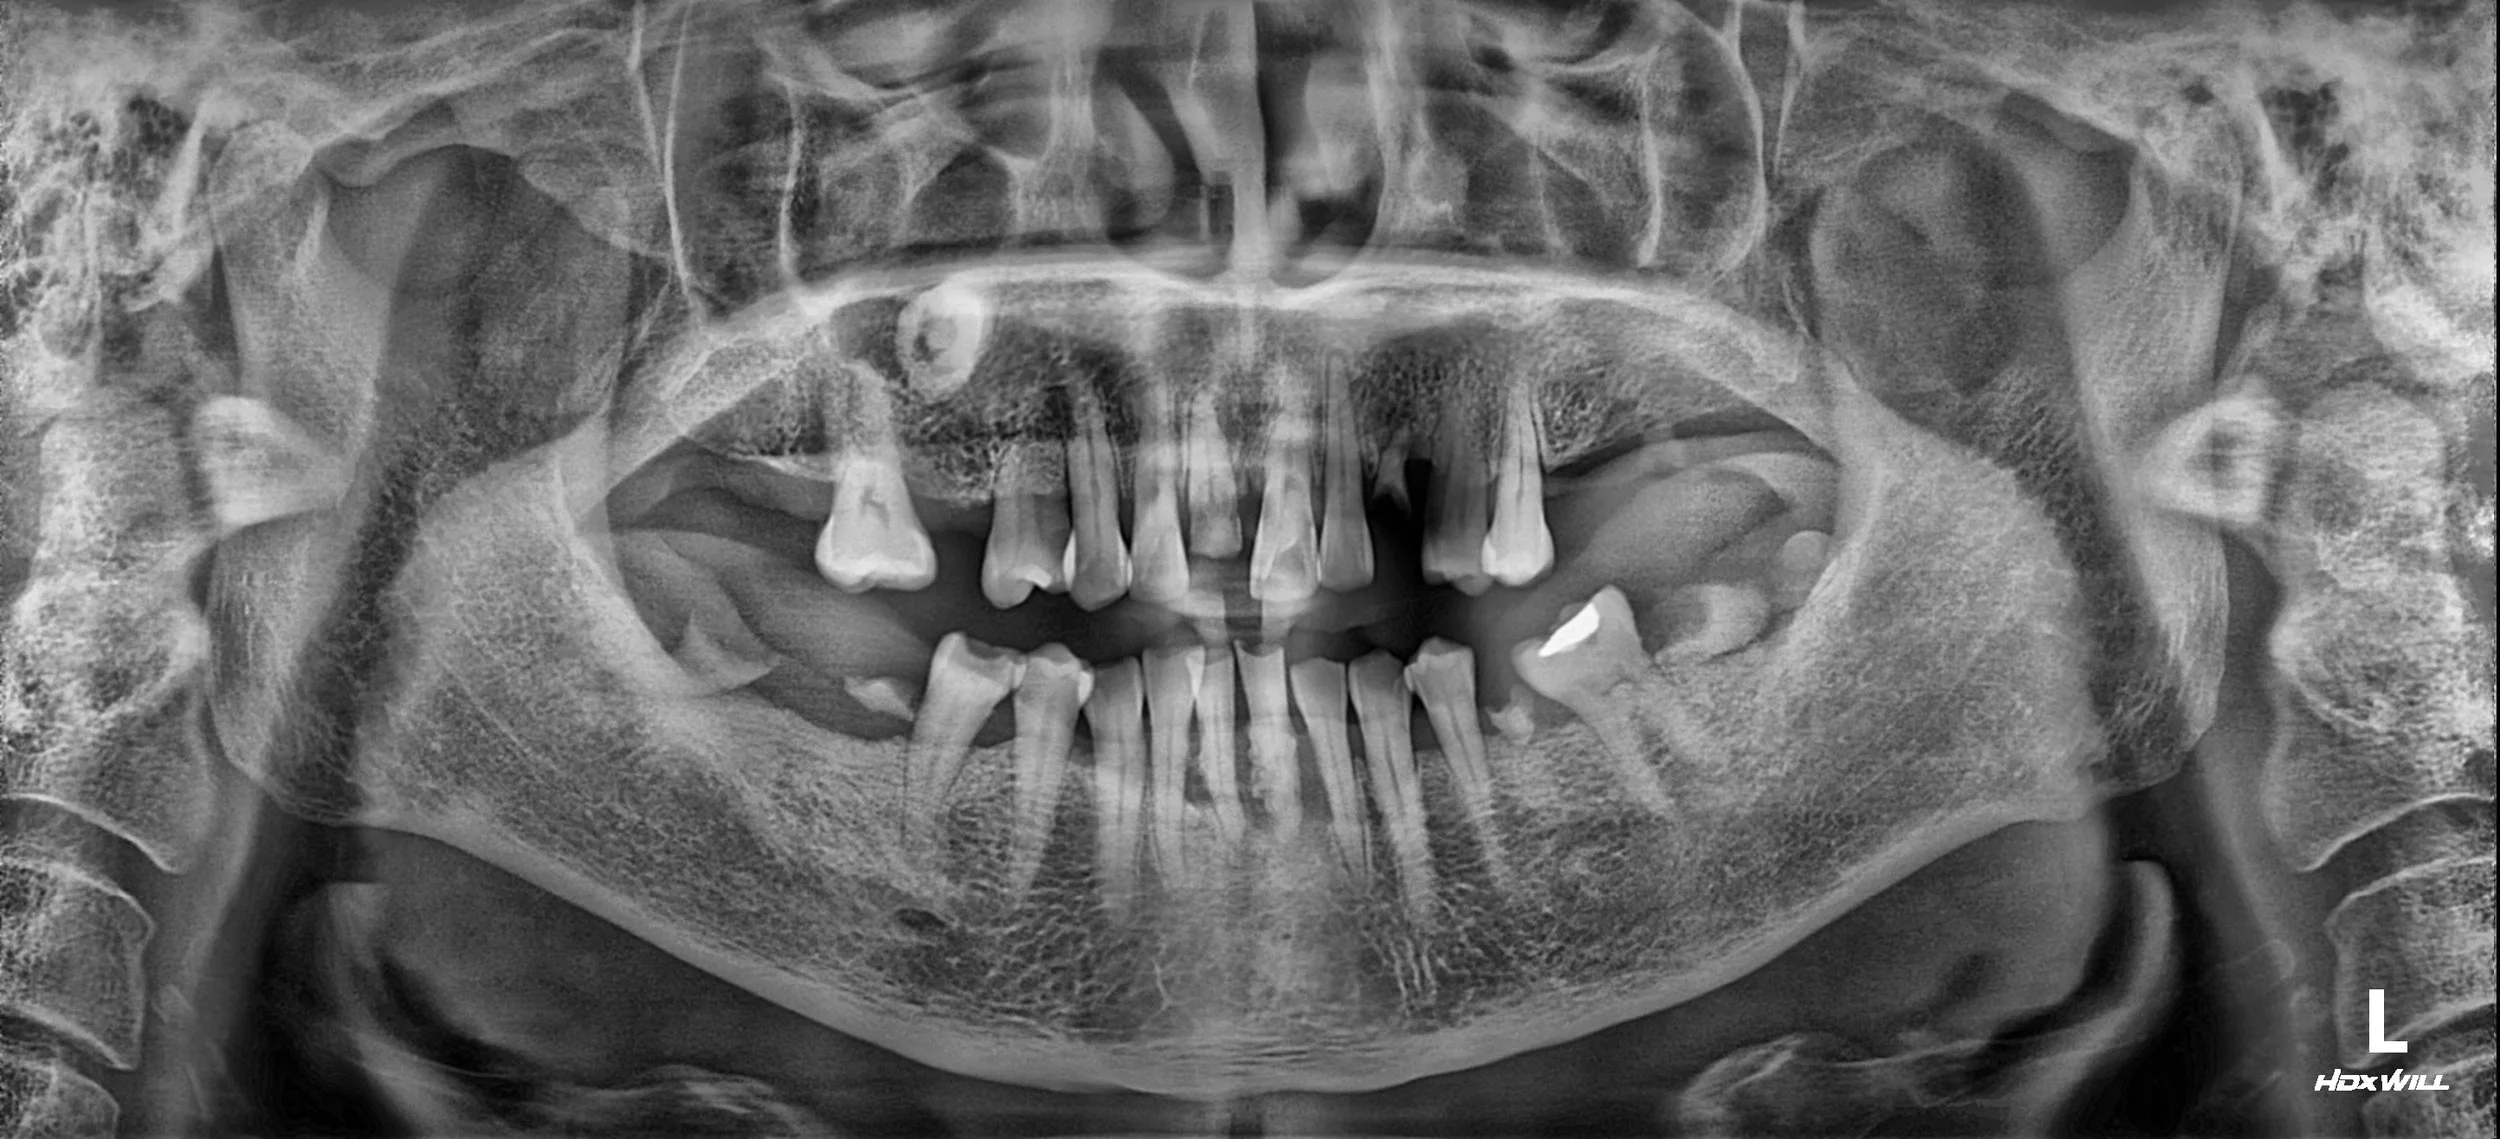

A female patient in her 50s presented with significant functional impairment due to extensive tooth loss, generalized severe periodontitis, and multiple dental caries. Her occlusal plane was completely collapsed, leading to an unstable bite and reduced chewing efficiency.

OPG - BEFORE